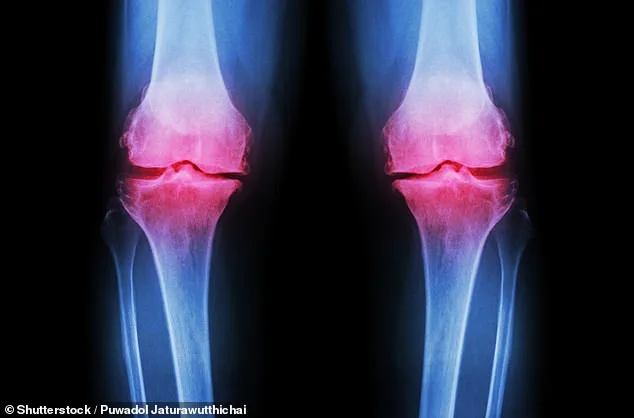

The decline in lipid metabolism during the 40s is particularly concerning. As people age, their bodies become less efficient at processing fats and sugars, increasing the risk of high cholesterol. This can lead to plaque buildup in arteries, straining the heart and raising blood pressure. Foods high in saturated fats—such as processed meats, dairy, and fried goods—exacerbate this issue. At the same time, bone density begins to decline, raising the risk of osteopenia, the early stage of bone thinning that can progress to osteoporosis. The Royal Osteoporosis Society (ROS) warns that one in two women and one in five men over 50 may suffer a fracture due to osteoporosis, calling it an 'escalating public health crisis.'

Prevention is key, experts say. Professor Hamish Simpson of Queen Mary University of London highlights that osteopenia is often 'a silent condition,' with symptoms only appearing after a fracture. 'Eating well, reducing alcohol intake, and increasing exercise can all reduce the risk of falls and fractures in later life,' says Dr. Richie Abel of Imperial College London. He recommends a calcium-rich diet from food sources like dairy rather than supplements, alongside vitamin D supplements. For bones, Simpson emphasizes the importance of 'loading exercises' such as jumping or skipping, which stimulate bone growth by creating small shocks to the skeleton.